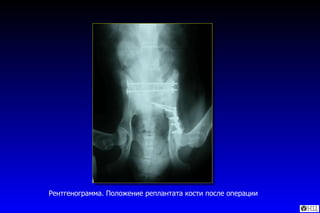

Рентгенограмма. Положение реплантата кости после операции

Остеосинтез реплантата